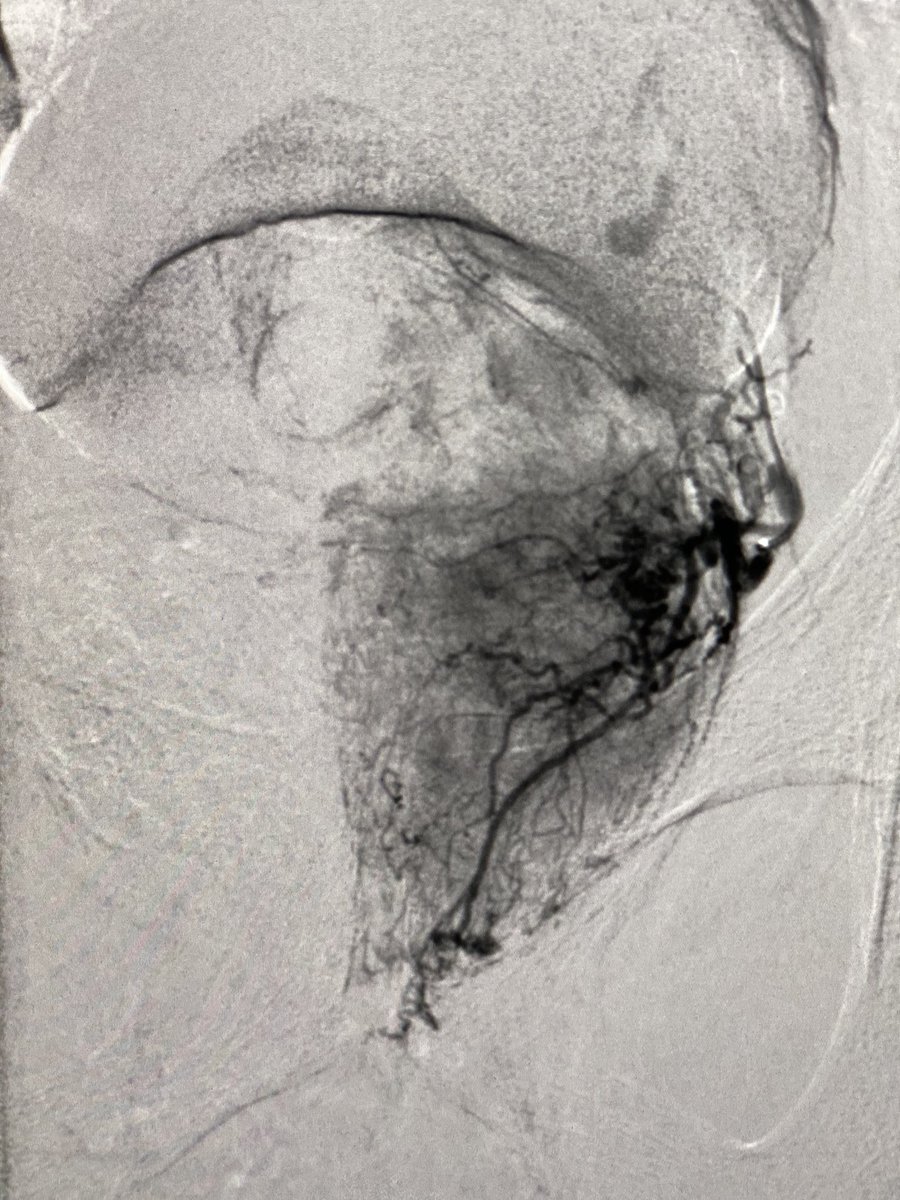

61yr with a whopping 306 cc prostate. #radialfirst #PAE. 1720 mGy. Discharged 90 min post #irad procedure. What’s the biggest prostate would you consider for PAE? @BSIR_News @pairsmedia @cirsesociety @AriIsaacsonMD @TiagoBilhim @BryantTimo